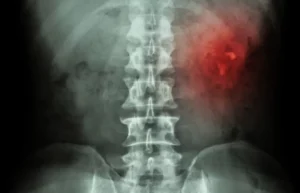

Homens, idosos, gravidas e crianças com sinais e sintomas de cistite deve procurar o seu médico ou um Urologista. Qualquer paciente com dor lombar e febre, deve procurar um médico imediatamente, pode ser bastante grave.